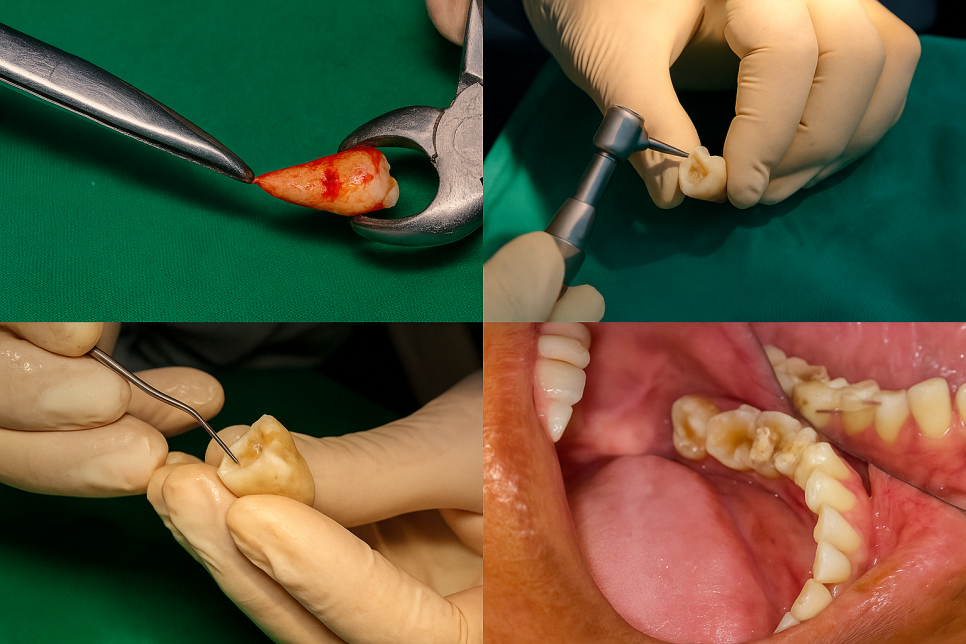

2️⃣ 지금부터는 한 사례를 예시로 들어

설명드리도록 하겠습니다.

위 사진은

좌측 아래 첫 번째 큰 어금니 사진으로,

과거에 신경치료를 진행했던 흔적이

남아있습니다.

이를 통해 치근단 병소가 확인되어

재감염이 최종 확인되었습니다.

다행히도 치주 인대와 잔존 뼈의 건강 상태가

양호한 편에 속해 재식을 진행하기로

결정하였습니다.

3️⃣ 참고로 이때 발치는

일반 기구가 아닌 특수 제작된 기구를

사용해 이루어집니다.

발치 후 염증이 위치한 부위를 잘라낸 후에

기존에 채워져 있던 재료를 일부 긁어냅니다.

4️⃣ 이후 긁어낸 자리 치근단 절제면을 통해

MTA(Mineral Trioxide Aggregate)라는

생체친화적 재료를 역충전합니다.

이를 통해 조직의 재건을 도울 수 있으며

술식의 성공률을 높여줄 수 있답니다.

이렇게 MTA 충전이 마무리된 부위를

원래의 치조와(잇몸뼈에 해당하는 홈)에

다시 심습니다.

그리고 안정적으로 자리 잡을 수 있도록

인접 부위에 일시 고정시킵니다.

이 모든 과정은

손상이 생기지 않도록 신중히,

그리고 30분 이내로 신속히 진행됩니다.